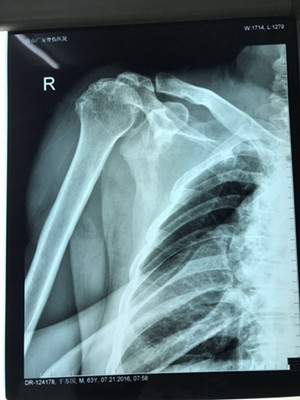

據(jù)了解,干大伯半年前因外傷導(dǎo)致頸椎外傷伴截癱,右肩關(guān)節(jié)脫位伴巨大肩袖斷裂,曾在廣安醫(yī)院接受頸椎手術(shù),術(shù)后恢復(fù)良好。后來,干大伯要求進(jìn)一步對肩關(guān)節(jié)進(jìn)行治療。廣安醫(yī)院副院長危立軍及運動醫(yī)學(xué)科主任羅軍對其進(jìn)行詳細(xì)檢查后,認(rèn)為干大伯的右肩存在巨大不可修復(fù)肩袖撕裂伴嚴(yán)重的關(guān)節(jié)炎,肩袖的脂肪浸潤達(dá)到四級,治療上有一定的挑戰(zhàn)性,只能通過特殊類型的人工肩關(guān)節(jié)——反式全肩人工關(guān)節(jié)來重建關(guān)節(jié)功能。